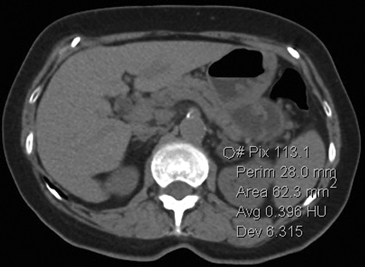

La presencia de lípidos intracelulares disminuye la densidad de la lesión debido a que estos son menos densos que el agua. El primer estudio en reportar la utilidad de la densitometría por TC en la diferenciación de una lesión suprarrenal benigna de una maligna fue el realizado por Lee et al6, utilizando la medición del coeficiente de atenuación o densidad de la lesión expresada en unidades Hounsfield (UH), en una TC no contrastada, demostrando que el coeficiente de atenuación promedio de los adenomas (2,2 UH) fue significativamente menor que la de las lesiones no adenomas (28,9 UH). Utilizando un punto de corte de 0 UH la sensibilidad de la TC no contrastada en la caracterización de un adenoma es cercana a un 47%, con una especificidad de aproximadamente 100% (Figura 9 a y b). Sin embargo, estudios posteriores7 han corroborado que al utilizar un punto de corte de 10 UH, la sensibilidad asciende a un 71%, y la especificidad se mantiene en prácticamente 98%, por lo que este umbral de densidad es el más utilizado en la actualidad. Es importante enfatizar que para una adecuada medición de la densidad, la región de interés (ROI) no debe incluir áreas de necrosis ni de hemorragia, y debe abarcar al menos la mitad o dos tercios de la lesión, para evitar el artefacto por ruido y el efecto de volumen parcial con el tejido adiposo adyacente (Figura 10).

Figura 10. Adenoma suprarrenal derecho. Lesión suprarrenal derecha, cuya densidad es consistente con un adenoma típico. En la imagen se demuestra una adecuada medición de la densidad lesional, con una región de interés (ROI) que abarca al menos dos tercios de ésta.

Los valores más utilizados son un 40% de lavado relativo de en fase tardía realizada a los 15 minutos y un lavado absoluto de 60%. De este modo cualquier lesión que muestre un lavado relativo mayor al 40% o absoluto mayor al 60% es consistente con un adenoma, con una sensibilidad y especificidad cercana al 100% (Figura 14 a, b y c). Dado la rapidez con que se obtiene un TAC de abdomen en la actualidad, algunos trabajos han recomendado utilizar cortes tardíos realizados a los 10 minutos, con el fin de optimizar el tiempo de examen, y utilizar un valor relativo de corte más conservador del 50%9.

A

B

C Figura 14. Tomografía computada de un adenoma suprarrenal izquierdo típico. Se ha colocado un circulo que representa la región de interés en la lesión de la glándula suprarrenal izquierda, obteniendo una medición promedio (Avg) expresada en unidades Hounsfield (UH). En fase precontraste (a) su densidad es de 0 UH, (flecha), en fase protovenosa (b) alcanza una densidad de 59 UH (cabeza de flecha), y en fase tardía (c) su lavado es de aproximadamente un 50%, llegando a una densidad de 30 UH.